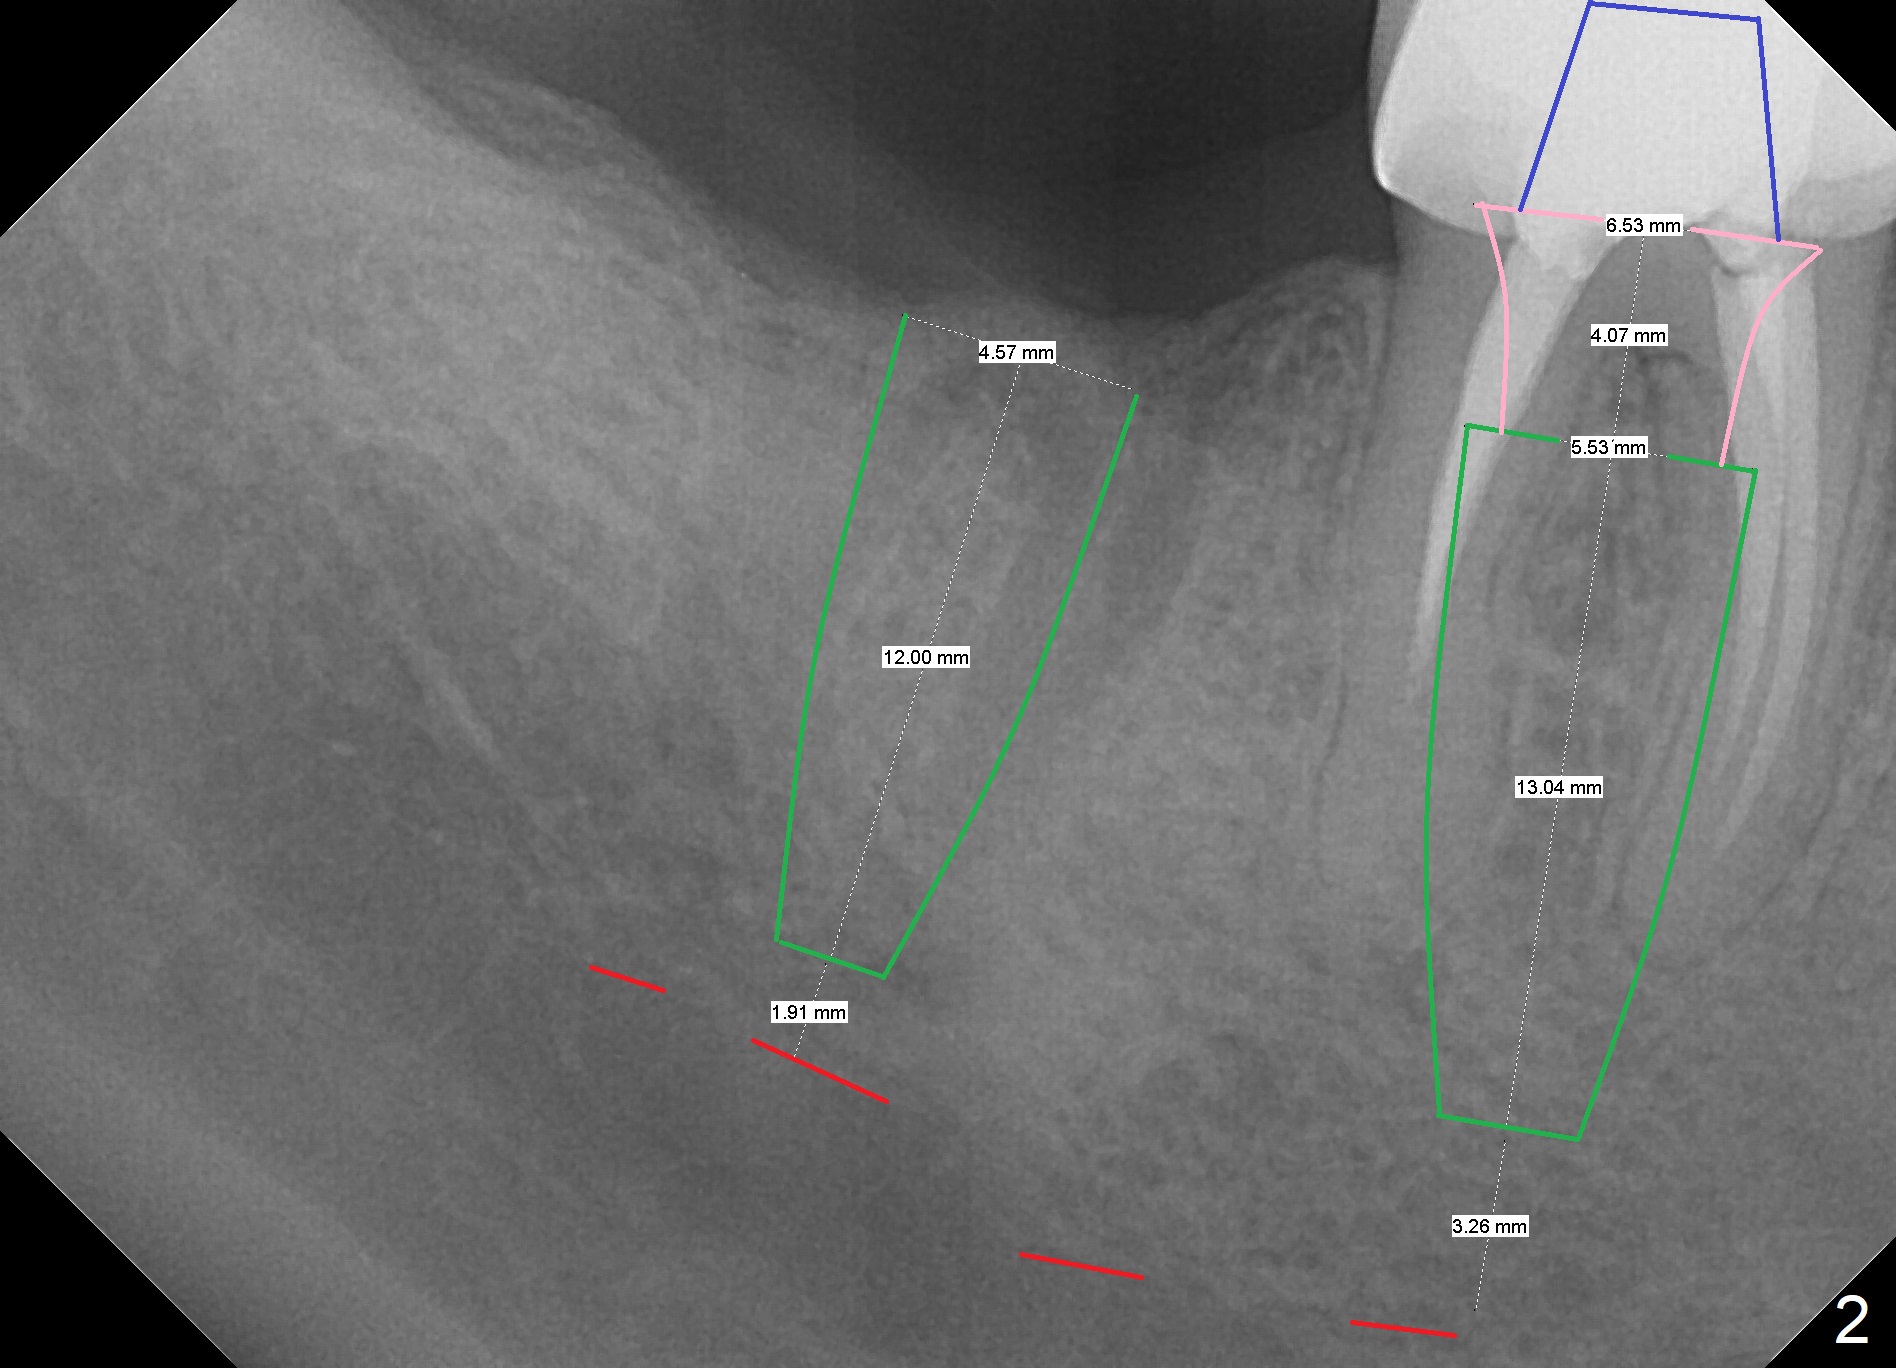

To quicken healing, an implant larger than 5.5 mm will be placed (Fig.2). To establish osteotomy in the relative narrow septum, it seems necessary to use Magic Drills sequentially instead of single fashion. Use of 4.8 mm MD in the pointed septal crest may create vibration and instability. The drill may drift into the mesial or distal socket.